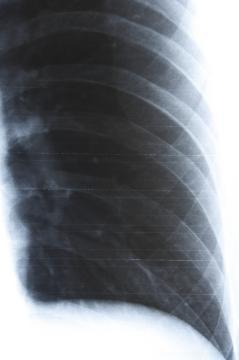

Dobrý den, už celé hodiny hledám lékařskou poradnu online, kde je možné odeslat z otázkou i obrázek. Chtěl bych Vás poprosit o přezkoumání snímku. RTG vzniklo po sedmi dnech úrazu. Smik jsem se na zamrzlé kaluži a měl jsem přitom ruku v kapse. Můj ošetřující lékař mi tvrdí, že na snímku je vše OK, přičemž snímek studoval 4 sekundy. Já se vůbec necítím že by bylo všechno v pořádku.POZNÁMKA: Snímek je na klasickém Filmovém materialu. Tento obrázek jsem získal pomocí silného zábleskového svetla. Píšu to proto, aby jste do úvahy vzali skutečnost, že to není originál. Podezřelé místo jsem vyfotografoval z blízka a zvýšil kontrast aby bylo možné vidět lépe tuto konkrétní část. Srdečně Vám děkuji za odpověď. Jaro.

Dobrý den, bohužel nejsem ortoped ani rentgenolog (a ani nikoho takového v poradně nemáme), ale z mého "laického" pohledu se mi nezdá horní okraj předposledního zobrazeného žebra - vypadá, že je nalomené. Co se týká odborného pohledu, je v podstatě jedno, zda-li jsou žebra naražená nebo zlomená (nalomená), protože léčba je stejná - klidový režim, co nejméně hýbat hrudníkem, tišení bolestí analgetiky. Zlomená žebra se do sádry nedávají, ani nijak nefixují. Všeobecně je známé pravidlo, že naražená žebra bolí více a déle než zlomená.